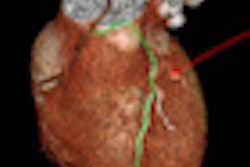

CCTA's key selling point is the potential of obtaining anatomic information about the coronary arteries noninvasively, reducing the need for subsequent cardiac testing. A negative CCTA confers a 99% likelihood of not having obstructive coronary artery disease. Still, a CCTA result "is not definitive evidence of obstructive disease," as CCTA is only 88% specific, and additional functional tests are sometimes needed, according to the authors.